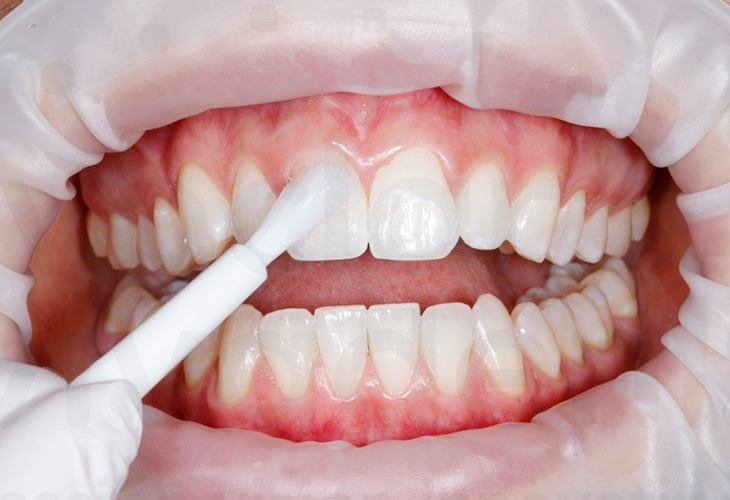

ЭТАП 2

Полировка зубов

Укрепление эмали

фторсодержащими

средствами

Реминерализация зубов